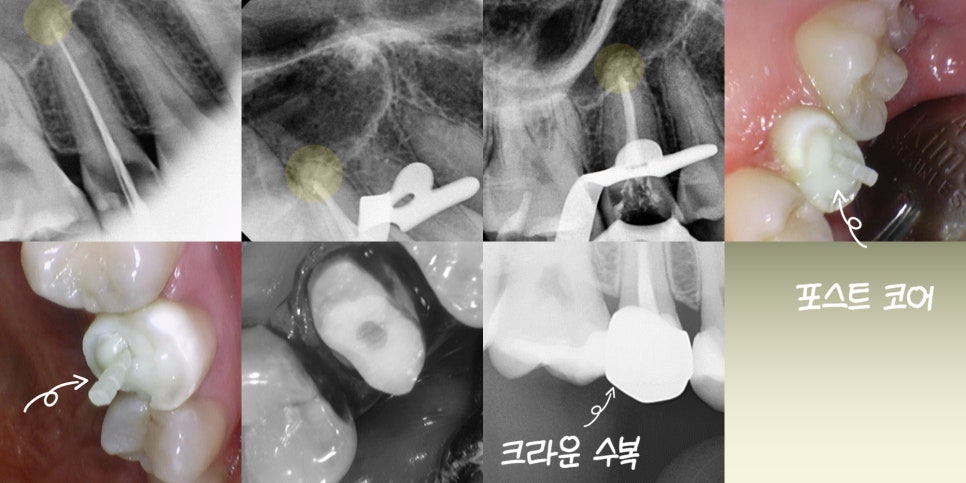

우식이 가장 깊은 경우

신경치료를 진행하게 됩니다.

겉으로는 미세한 충치처럼 보여도

치아 내부를 들여다보면

안은 훨씬 범위가 넓게 썩어 있는 것을

확인할 수 있게 됩니다.

우식 부위를 삭제하면서 근관을

찾고 내부를 확장과 괴사 조직 제거를

통해 깨끗하게 만듭니다.

이때 중요한 것이 감염 조직을

남기지 않는 것입니다.

또, 약해진 치질을 보존하기 위해

포스트(Post)를 사용하기도 합니다.

*포스트는 근관 내부에 심어 치아를

지지해 주는 기둥과 같은 역할을 합니다.

이후 빠른 시일 내로 크라운을 씌워 정상적인

식사가 가능하도록 합니다.